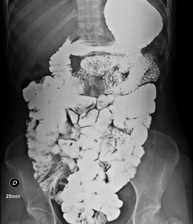

- RX Abdomen

Tècnica que usa els raigs X a través de la qual s'obtenen imatges de l'abdomen (estómac, intestí prim, intestí gros, fetge, ronyons, bufeta, pelvis òssia, etc.) per al seu estudi. - RX Columna lumbar

Prova diagnòstica que consisteix en obtenir imatges radiològiques en moviment de l'esòfag, estómac, duodè i intestí prim mitjançant l'ús de raigs X (fluoroscòpia) i d'un contrast opac baritat que s'administra per via oral. - Ènema opac doble contrast

Prova diagnòstica que consisteix en obtenir imatges radiològiques de l'intestí gros (còlon i recte) mitjançant l'ús de raigs X. S'utilitza un contrast opac que s'administra a través del recte en forma d'ènema i també s'introdueix aire per expandir el còlon.

Una radiografia de tòrax és una tècnica mitjançant la qual, amb l'ús d'una petita dosi de radiació, s'obté una imatge bidimensional de la caixa toràcica i el seu contingut (pulmons, cor, mediastí, etc. ). És una de les proves mèdiques realitzades més comuna. - RX Abdomen

Una radiografia d'abdomen és una tècnica mitjançant la qual, amb l'ús d'una petita dosi de radiació, s'obté una imatge bidimensional de l'abdomen amb les seves estructures anatòmiques (estómac, intestí prim, intestí gros, fetge, pàncrees, ronyons, bufeta, pelvis òssia, etc.) - Telerradiologia columna